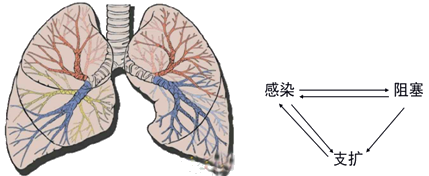

支氣管擴(kuò)張大多繼發(fā)于急、慢性呼吸道感染和支氣管阻塞。

『答案解析』支氣管擴(kuò)張大多繼發(fā)于急、慢性呼吸道感染和支氣管阻塞。